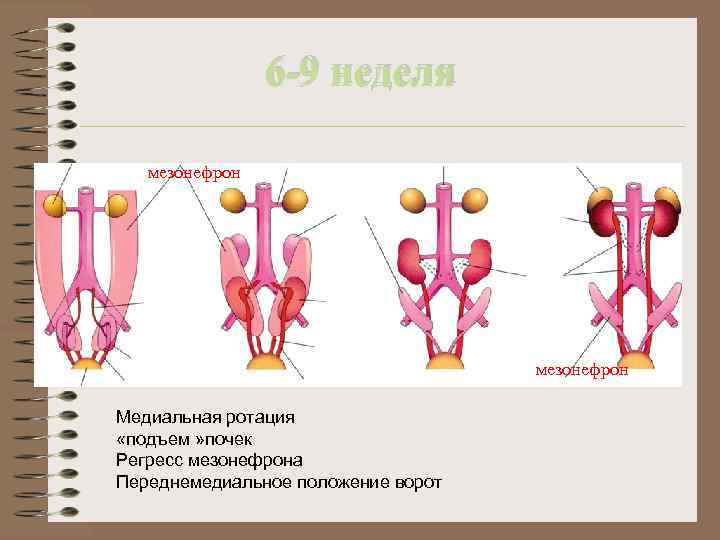

6 -9 неделя мезонефрон Медиальная ротация «подъем » почек Регресс мезонефрона Переднемедиальное положение ворот